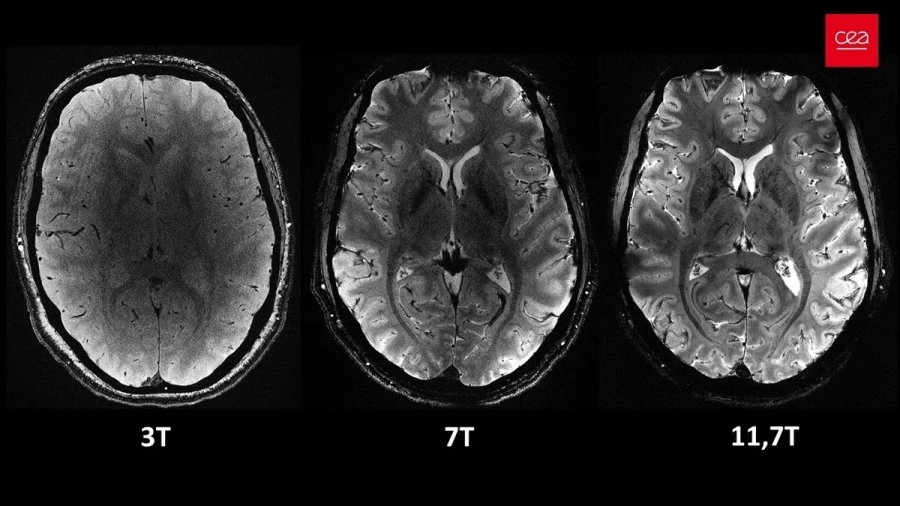

Οι σαρωτές μαγνητικής τομογραφίας περιβάλλουν το σώμα (ή το μέρος του σώματος που θέλετε να απεικονίσετε) με ένα ισχυρό μαγνητικό πεδίο. Οι περισσότεροι σαρωτές που χρησιμοποιούνται σήμερα μπορούν να επιτύχουν ένταση πεδίου 1,5 ή 3 teslas (T). Το μηχάνημα μαγνητικής τομογραφίας Iseult, που είναι υπεύθυνο γι’ αυτές τις φωτογραφίες, μπορεί να φτάσει στα 11,7 Τ!

Πρακτικά αυτό σημαίνει ότι αυτή η εξαιρετική ανάλυση μπορεί να επιτευχθεί σε ένα κλάσμα του χρόνου που θα χρειαζόταν για έναν σαρωτή 1,5 ή 3Τ.

Μπορείτε να δείτε ξεκάθαρα τη διαφορά μεταξύ του τυπικού σαρωτή 3Τ στα νοσοκομεία, ενός σαρωτή 7Τ που μόνο ορισμένοι τυχεροί ερευνητές έχουν στα χέρια τους και του νέου σαρωτή των 11,7Τ.